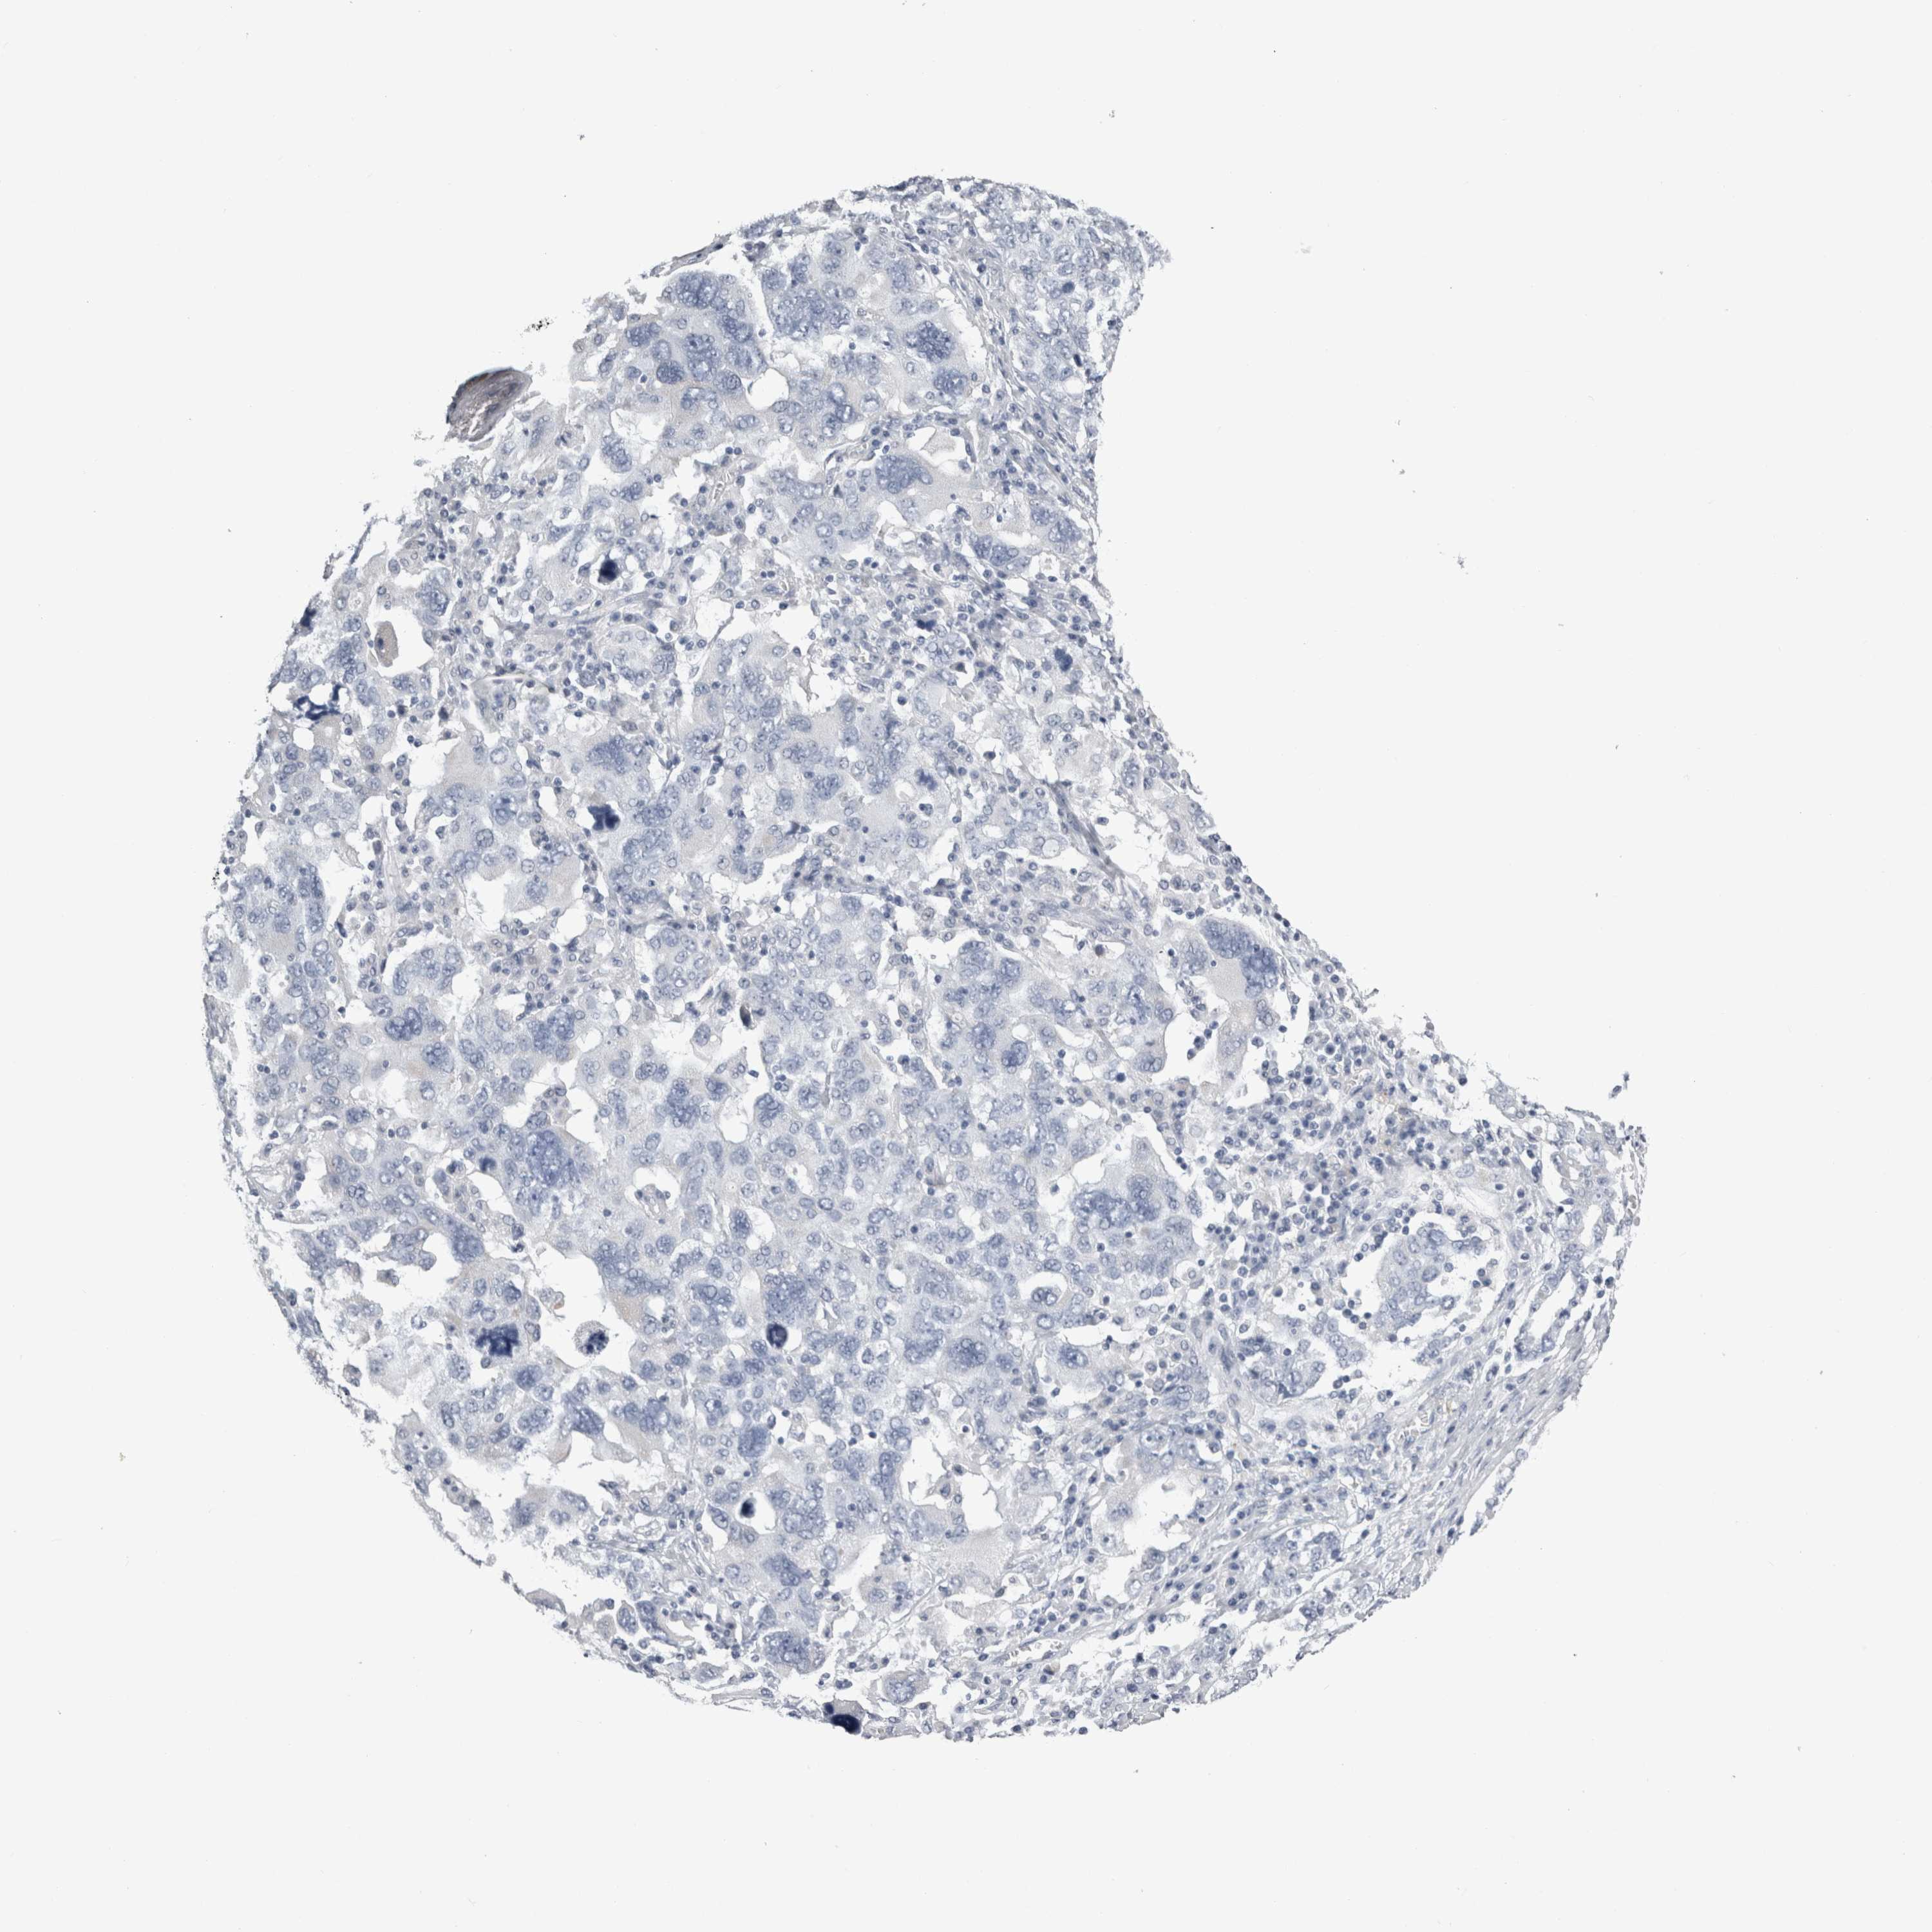

OVARIAN CANCER - Protein expressioni

A mouse-over function shows sample information and annotation data. Click on an image to view it in a full screen mode. Samples can be filtered based on level of antibody staining by selecting one or several of the following categories: high, medium, low and not detected. The assay and annotation is described here.

Note that samples used for immunohistochemistry by the Human Protein Atlas do not correspond to samples in the TCGA dataset.

Antibody stainingi

Antibody staining in the annotated cell types in the current human tissue is reported as not detected, low, medium, or high, based on conventional immunohistochemistry profiling in selected tissues. This score is based on the combination of the staining intensity and fraction of stained cells.

Each image is clickable and will lead to virtual microscopy that enables deeper exploration of all samples and also displays staining intensity scores, fraction scores and subcellular localization as well as patient and tissue information for each sample.

Antibody HPA026292

Antibody HPA055414

Cystadenocarcinoma, serous, NOS

Carcinoma, endometroid

Cystadenocarcinoma, mucinous, NOS

Carcinoma, NOS